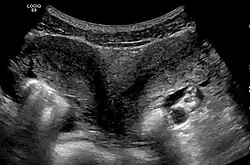

Diagnose

Die Diagnose wird in der Regel durch Sonografie gestellt.